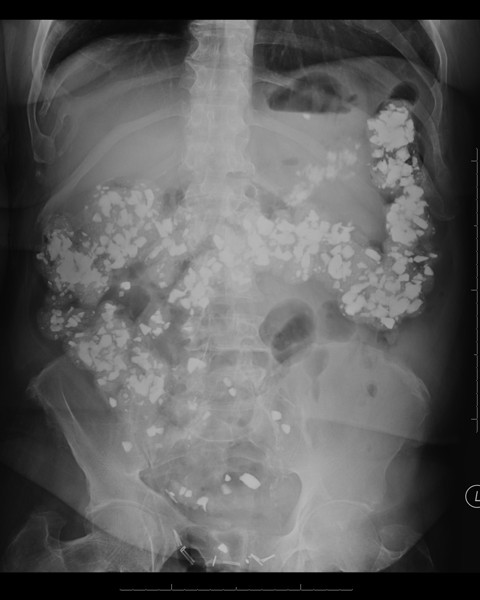

pica

psychological disorder or intentional & craving comsumption of non-nutritive substances over a period of time

patient w/ pica

what is this an image of?